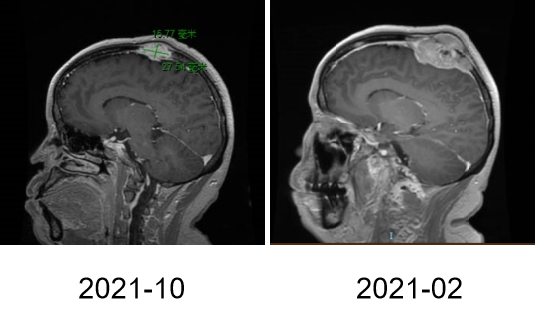

图2A

图2B